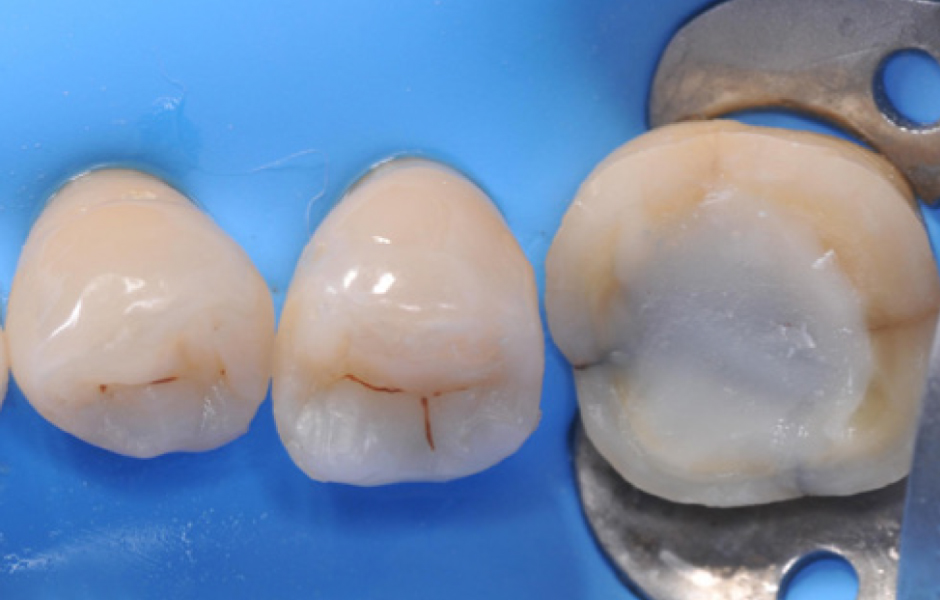

Obr. 1: Výchozí situace. Výchozí situace se týká staršího pacienta se starými amalgámovými výplněmi v pravém dolním distálním úseku, které si pacient přál odstranit z estetických důvodů.

Obr. 2: Nasazení kofferdamu. Po nasazení kofferdamu byly staré výplně odstraněny a objevil se skutečný rozsah ztráty tvrdých zubních tkání.

Obr. 3: Preparace kavit. Konečný stav preparací kavit: Byly dokončeny dvě kavity II. třídy a u prvního moláru byla provedena preparace pro overlay. Infrakce na meziální stěně moláru zůstala nedotčena; aby se zabránilo její další propagaci. Bude zpevněna při cementaci nepřímé rekonstrukce.

Obr. 4: Okamžité utěsnění dentinu. Obnažený dentin prvního moláru byl okamžitě ošetřen sealerem a byla provedena dostavba za použití SimpliShade Bulk Fill Flow (Kerr). Následně byly na premoláry umístěny dvě sekční matricové pásky pro postranní úsek, fixované oranžovým klínkem a kroužkem, pro zhotovení výplní II. třídy.